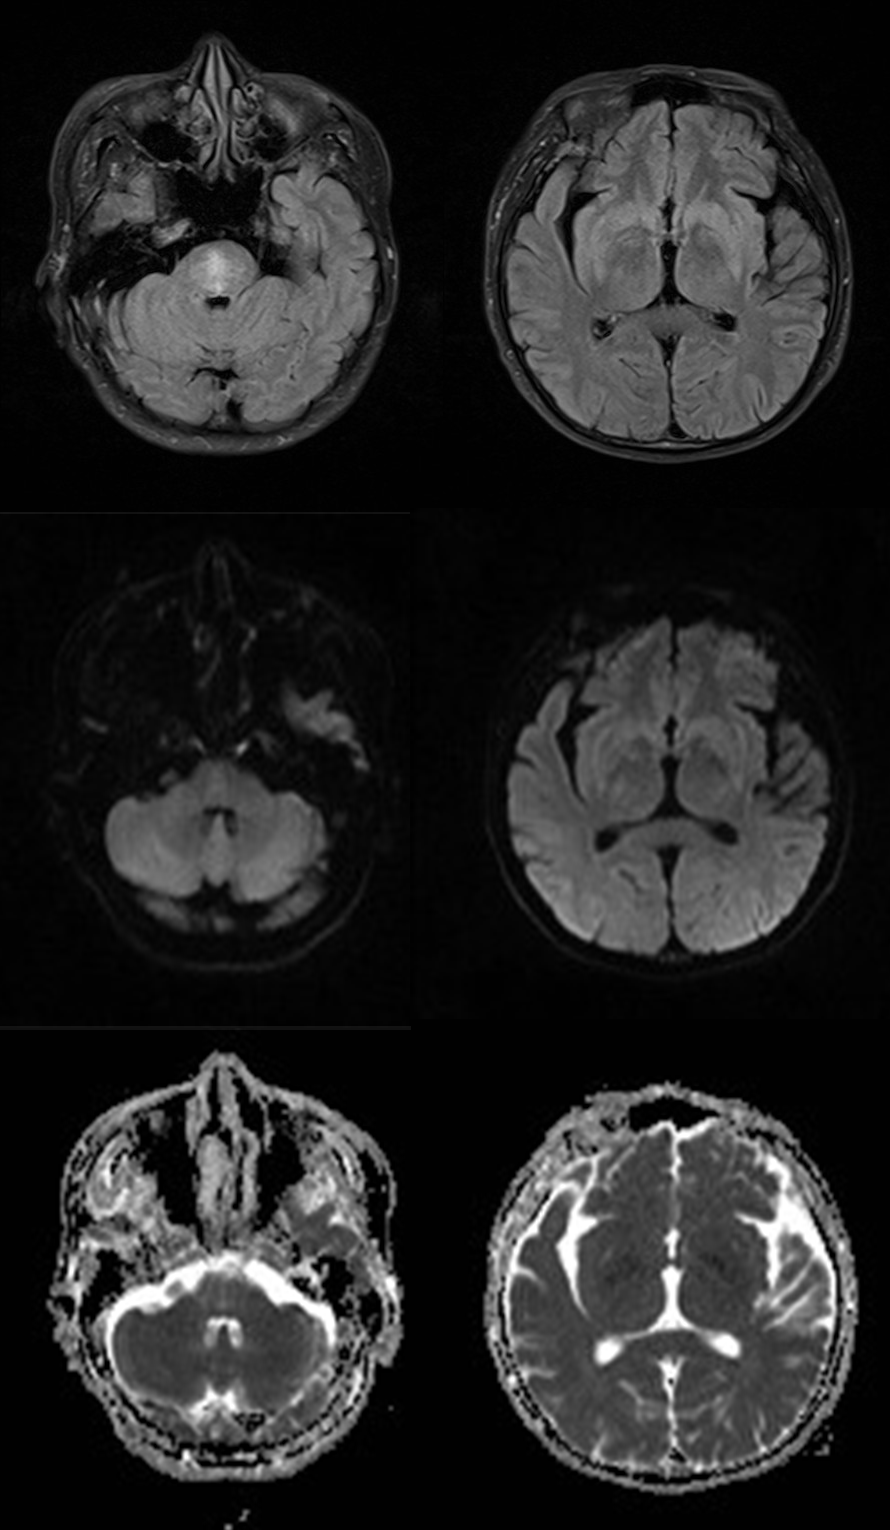

(4)CPM+EPM:(2) (3),MRI 与临床表现不密切相关,一般都会滞后几个星期。

桥脑“三叉戟”+基底核团+丘脑+皮层受累,扩散受限